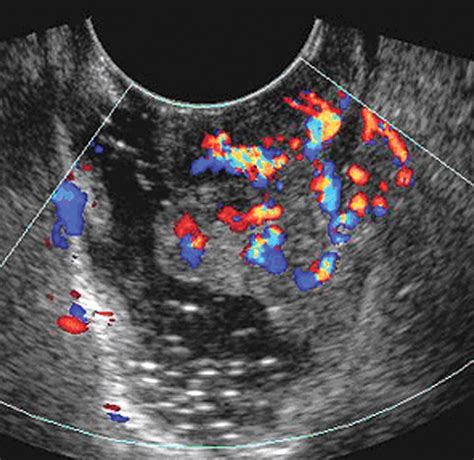

• Increased Vascularity: Using Doppler ultrasound, doctors can assess blood flow. Cancerous tumors often create their own blood supply, leading to irregular or high-velocity blood flow patterns.

• ovarian cancer ultrasound color doppler